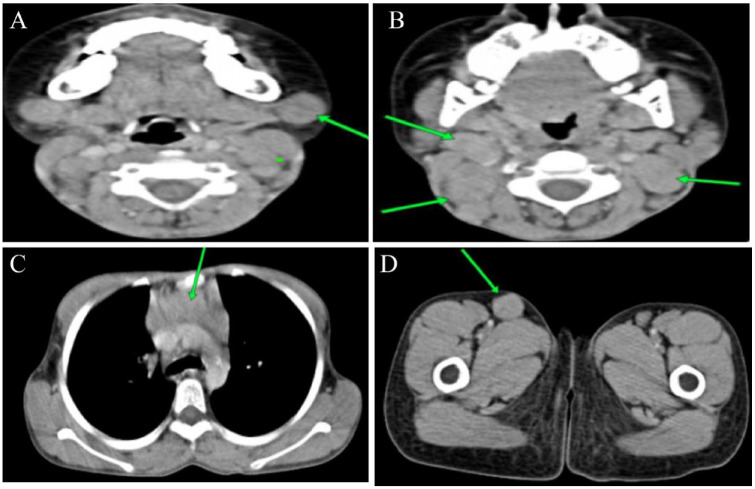

Rosai Dorfman disease (RDD) is a rare non-Langerhans histiocytic disorder, which belongs to the R group of the 2016 revised histiocytic classification. It's characterized by the accumulation of activated histiocytes in the sinusoids of lymph nodes and/or extranodal tissues. Herein, we report a 7-year-old female who was initially suspected to have a lymphoma but was later identified as having RDD. She presented with a history of fever, night sweats, and weight loss, and on physical examination had bilateral cervical lymphadenopathy. Histologic examination of the biopsied cervical lymph nodes showed distended sinuses with S100 and CD68 immunoreactive histiocytes demonstrating emperipolesis, confirming a diagnosis of RDD. The condition is known to be self-limiting. However, evidence from literature and our case management shows that medical therapy can hasten remission in pediatric cases.